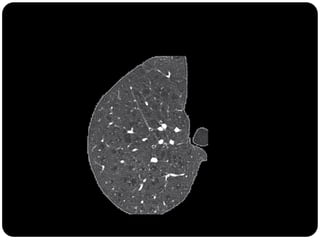

Lóbulo pulmonar secundário

Menor porção do pulmão, ainda circundada por um septo de

tecido conjuntivo;

Composto por 3 a 5 bronquíolos terminais (3 a 12*)

Identificado na TCAR tanto em estados normais quanto

patológicos;

Revestidos por septos interlobulares que contém as tributárias das

veias periféricas e dos vasos linfáticos;